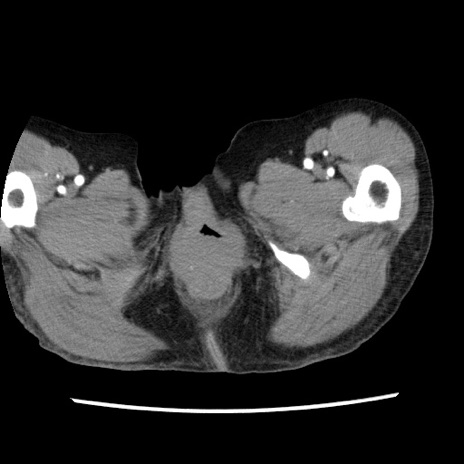

矢状断像

【症例】80歳代女性

【主訴】腹痛

【現病歴】8時間前から腹痛あり来院。

【既往歴】糖尿病、脂質異常症、子宮体癌にて子宮全摘術

【身体所見】意識清明・会話良好だが腹痛で苦悶様、全腹部にわたって反跳痛と圧痛あり

【データ】WBC 13600、CRP 0.14、LDH 224、CK 90